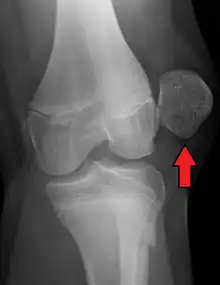

| X-ray showing a patellar dislocation, with the patella out to the side. | |

A patellar dislocation typically occurs when the knee is straight and the lower leg is bent outwards when twisting.[1][2] Occasionally, it occurs when the knee is bent and the patella is struck directly.[1] Commonly associated sports include soccer, gymnastics, and ice hockey.[2] Dislocations nearly always occur away from the midline.[2] Diagnosis is typically based on symptoms and supported by X-rays.[2]

Displacement of the patella laterally out of its groove strains the medial stabilizing connective tissues, particularly the medial patellofemoral ligament (supporting 50–80% of the knee mechanisms in lateral patellar glide), which is torn usually at its femoral attachment.[3] Traumatic patellar dislocation may cause bleeding into the joint space, ligament and muscle attachment tearing, and fracture of the medial wing of the patella.[3] Fracture of the weight-bearing portion of the lateral femoral condyle occurs in 25% of traumatic patellar dislocations.[3] Surgical repair of the patellar stabilizing structures – the medial patellofemoral ligament and vastus medialis muscle – may be needed for athletes.[3]